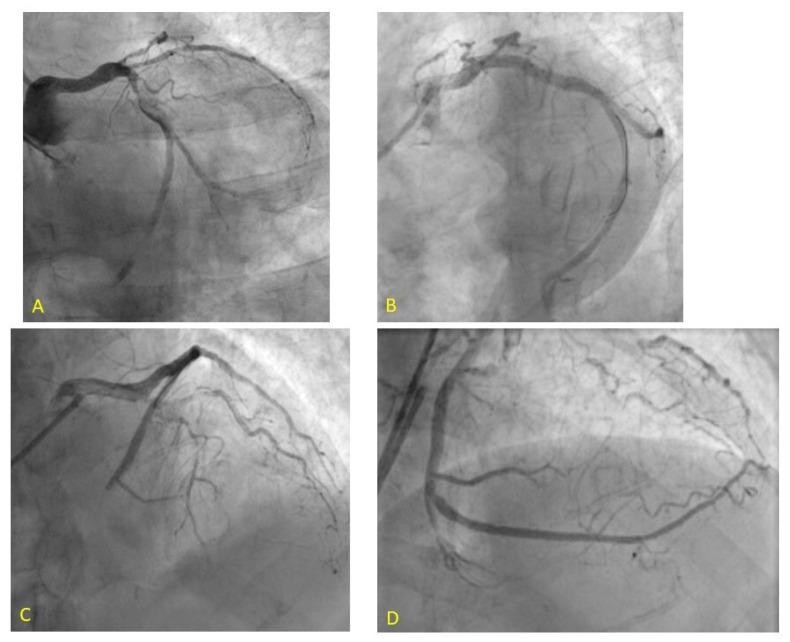

Primary percutaneous angioplasty (pPCI), represents the reperfusion strategy of choice for patients with STEMI according to current international guidelines of the European Society of Cardiology. Coronary no-reflow is characterized by angiographic evidence of slow or no anterograde epicardial flow, resulting in inadequate myocardial perfusion in the absence of evidence of mechanical vessel obstruction. No reflow (NR) is related to a functional and structural alteration of the coronary microcirculation and we can list four main pathophysiological mechanisms: distal atherothrombotic embolization, ischemic damage, reperfusion injury, and individual susceptibility to microvascular damage. This review will provide a contemporary overview of the pathogenesis, diagnosis, and treatment of NR.

根据欧洲心脏病学会当前的国际指南,直接经皮冠状动脉介入治疗(pPCI)是ST段抬高型心肌梗死(STEMI)患者的首选再灌注策略。冠状动脉无复流的特征是造影显示心外膜前向血流缓慢或无血流,导致在没有机械性血管阻塞证据的情况下心肌灌注不足。无复流(NR)与冠状动脉微循环的功能和结构改变有关,我们可以列出四种主要的病理生理机制:远端动脉粥样硬化血栓栓塞、缺血损伤、再灌注损伤以及个体对微血管损伤的易感性。本综述将对无复流的发病机制、诊断和治疗进行当代概述。